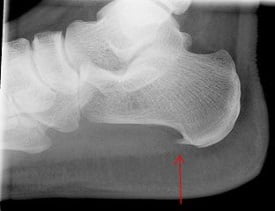

Пяточная шпора — так в народе называют воспалительно-дегенеративный процесс в мягких тканях, окружающих пяточный бугор. Сама по себе пяточная шпора не является отдельным заболеванием, это синдром, который возникает при некоторых патологических состояниях. Его суть заключается в разрастании костной ткани пяточной кости.

Нарост имеет четко определенную локализацию — плантарная поверхность пяточной кости, в области прикрепления длинной связки стопы. Размеры нароста могут колебаться в незначительных пределах, а форма напоминает шпору.

Почему развивается пяточная шпора, и что это такое? Образование шпоры на пяточной кости начинается с возникновения плантарного фасциита. Сначала воспаляется фасция — соединительная ткань подошвы, которая расположена около пяточного бугорка и доходит до пальцев стопы. Затем, если процесс затягивается, происходит кальциноз — пропитка воспаленного участка солями кальция. Так образуется остеофит, который из-за своего характерного вида получил в народе название «шпора».

Пяточная шпора: фото

Как выглядит пяточная шпора, предлагаем к просмотру подробные фото.